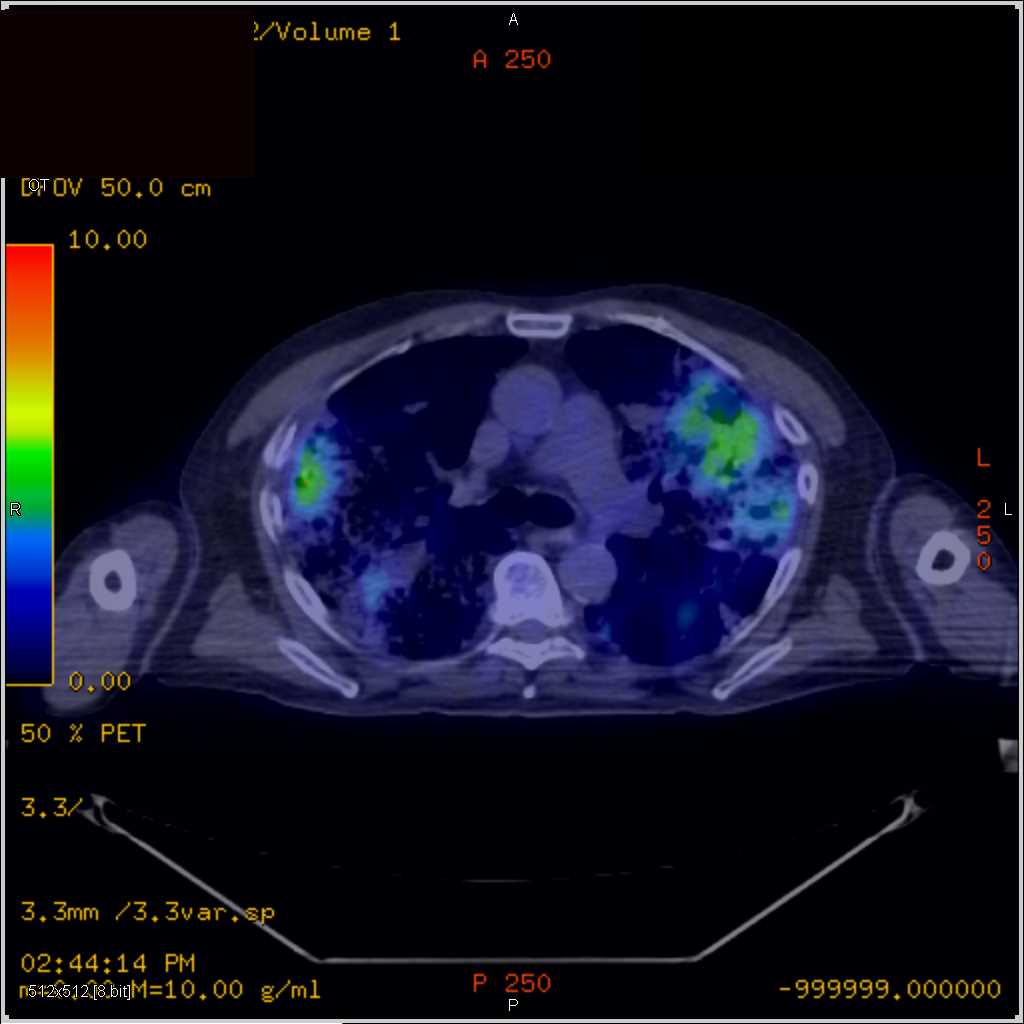

Septic Emboli on PET CT